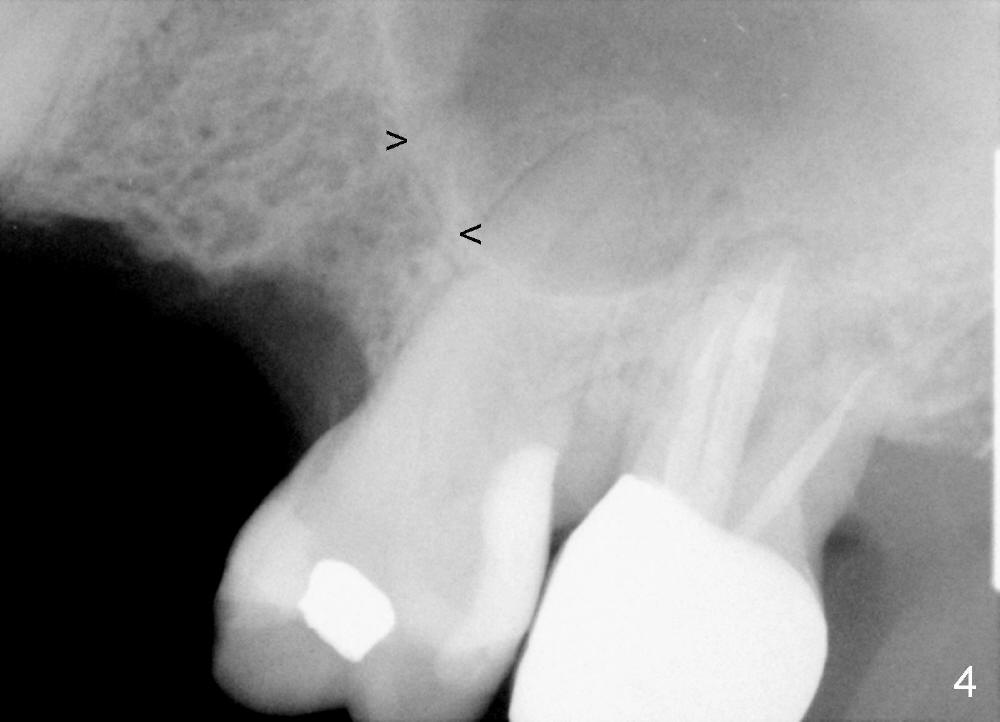

The anterior retainer is kept as a crown at #11 (Fig.2: C), whereas the residual root at the site of #13 is extracted with apical perforation (Fig.3 ^).  It is confirmed by Fig.4 (<).  To close the perforation, an osteotomy is initiated on the palatal wall of the socket with a 2 mm osteotome (Fig.5 insert: circle).  As the osteotomy is being enlarged by a 3 mm osteotome, the bone between the original socket and the osteotomy is being pushed buccally.  The former is being closed (Fig.5).  The osteotomy is finished with combination of osteotomes and reamers.  Fig.6 shows that a 5x14 mm tap is inserted at the site of #13 and that the sinus floor is lifted.  In fact the sinus membrane is partially torn at the osteotomy, which is repaired by insertion of Colla-form Dressing (Impladent), followed by autogenous bone (harvested from reamers) mixed with Osteogen  (Impladent).  A 5x14 mm implant is placed at the site of #13 with insertion torque more than 60 Ncm (Fig.7: I).  An incision is made at the site of #12 to start osteotomy with insertion of a parallel pin (Fig.7 P).  A 3 mm reamer is kept in place for position confirmation (Fig.8 R).  Due to ridge atrophy (Fig.2 arrowheads), a much smaller, but longer implant is placed at the site of #12 (Fig.9: 4x17 mm).  The autogenous bone harvested from #12 osteotomy is placed in the buccal gap of #13, followed by insertion of Colla-form Dressing (Fig.10 M).  To protect the membrane, a short abutment (4x3 mm) is temporarily placed (Fig.9,10 A) and perio dressing (Fig.9 D) is applied around the abutment and the interproximal areas of the neighboring teeth.  Usually perio dressing dislodges around 1 week postop, particularly for a large edentulous space.  In this case, the dressing is quite stable 11 days postop: the abutment (Fig.11 A) appears to contribute to retention of the dressing (D).